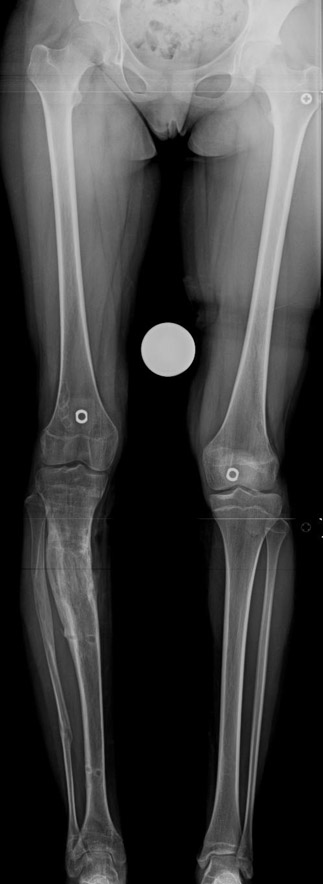

The bifocal compression technique described by Ilizarov, which consists of acute shortening and gradual distraction, allows acute shortening of 4-5 centimeters in tibial defects; defects exceeding this amount can be further shortened gradually by 3 millimeters per day. The same principle is also applicable to the femur, allowing an acute shortening of 8 centimeters. This method facilitates reconstruction of bony continuity and primary or delayed primary closure of soft tissue defects, which would would avoid the requirement for free flaps. A second corticotomy in the metaphyseal region may be used to restore the original length of the shortened bone and to increase it’s vascularity. Intramedullary osteosynthesis of intra-/periarticular fractures is a borderline indication. Open reduction and internal fixation of these fractures hazards the blood supply to (small) bone fragments by extensive dissection, and nonunion or infection is (iatrogenically) invited. In contrary, percutaneous or indirect reduction by limited dissection, small wire and percutaneous cannulated screw osteosynthesis, augmented by external fixation, provides a stable construction to allow early mobilization, range of motion exercises and sometimes partial weight bearing.

My preference in these cases is to use circular external fixators, which are modular, permit fixation of small reduction wires to the frame, and enable postoperative angular adjustments. Recently, combined techniques using external fixators and intramedullary rods have been introduced. The advantage of this method is to decrease the external fixation time by about 50% and to enhance the patient’s comfort.

Case 1